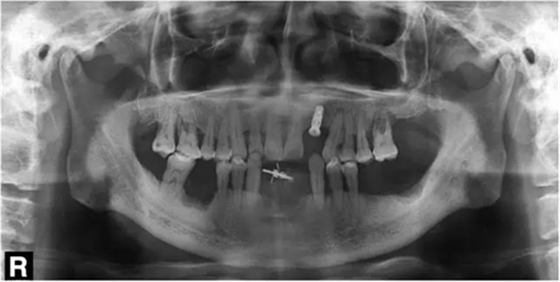

行影像學(xué)檢查(圖2);種植一枚Zuga 3.5*10 mm種植體,扭力≥35 N•cm,旋入愈合基臺(tái)(healing abutment)(圖3、4)。

圖4 種植術(shù)后影像學(xué)檢查

3個(gè)月后,分別使用傳統(tǒng)的轉(zhuǎn)移桿硅橡膠取模以及口內(nèi)掃描取模進(jìn)行修復(fù)(圖5~8)。